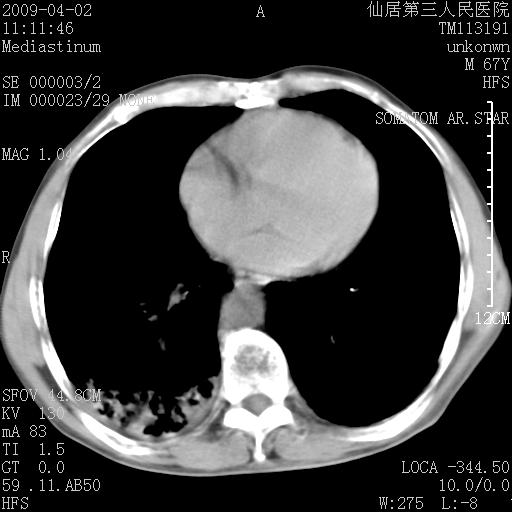

患者老年男性,乏力畏寒来诊,摄胸片示右下肺感染性病变,抗炎两周后复查胸片,无好转有进展。

后做ct平扫表现如下:

病灶呈蜂窝征,纵隔多个淋巴结肿大;肺泡癌需考虑

我认为普通的感染应该可以除外,间质性肺炎可能性较大,但如何解释纵膈的淋巴结肿大呢

考虑双肺间质性改变(间质纤维化?)伴右肺下叶感染。